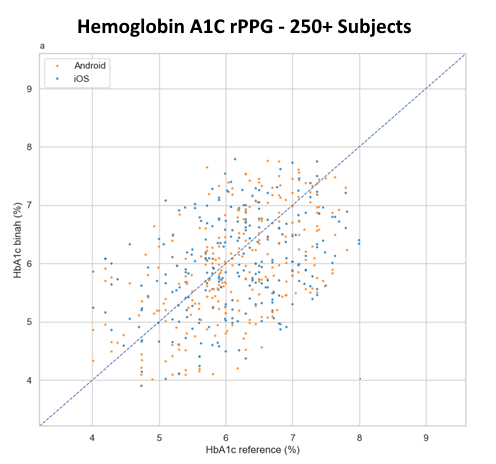

Briah.ai’s technology can measure blood pressure, heart rate, heart rate variability, respiration rate, hemoglobin, and hemoglobin A1C.

How accurate are the measurements provided by Briah.ai?

Our technology meets high accuracy standards and has been validated through extensive research and testing.